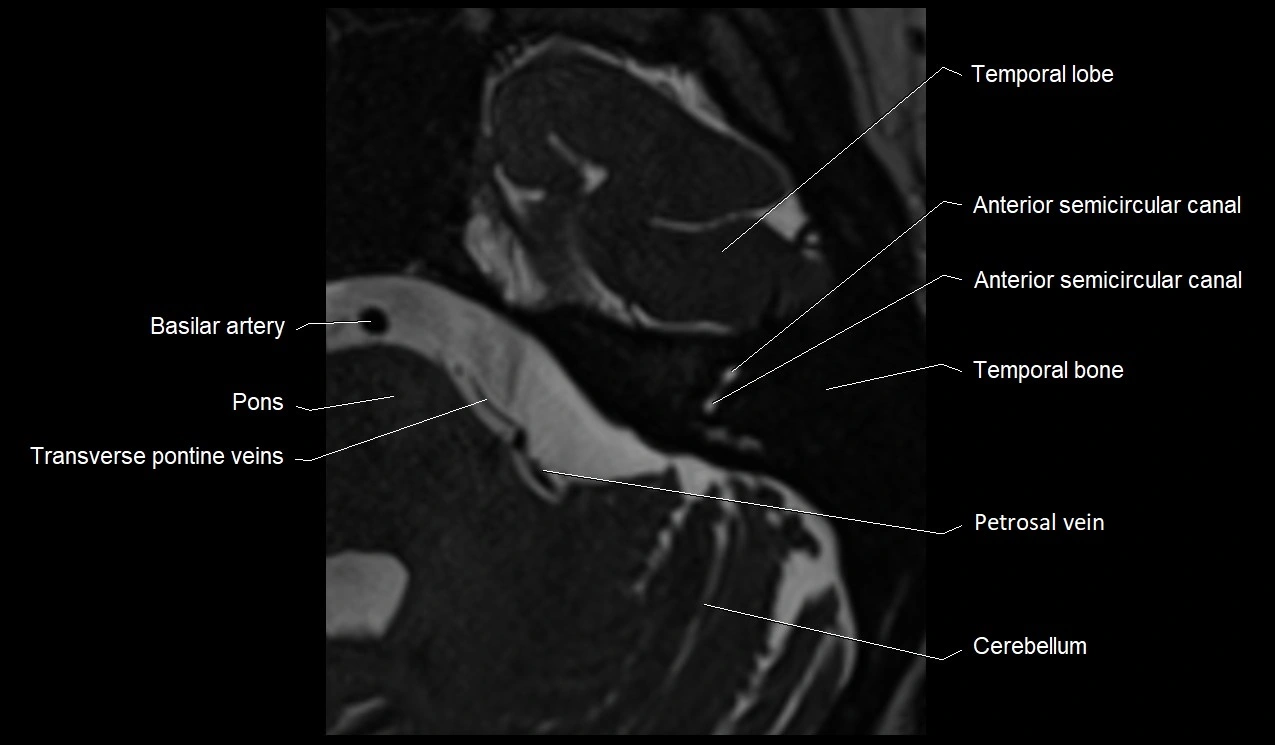

image